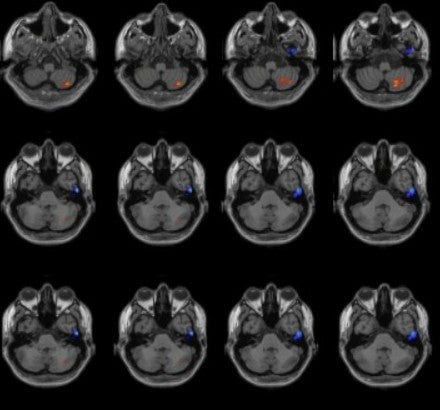

Veränderte funktionelle Netzwerkmuster im Gehirn bei Patienten mit Migräne ohne Aura nach transkutaner Stimulation des Nervus.